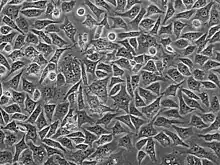

PC-3細胞睾丸激素5α還原酶及酸性磷酸酶的活性低,並且不會表達前列腺特異抗原。有核型分析報告表明PC-3細胞是近三倍體的,具有62條染色體,當中並沒有Y染色體的存在。電子顯微鏡顯示PC-3細胞表現出低分化腺癌的特徵,並且具有上皮起源的贅生性細胞共有的特徵,例如許多微絨毛、接合複合物、異常的細胞核、核仁及線粒體、環孔片層及脂質體。這些細胞對雄激素、糖皮質激素及成纖維細胞生長因子並没有任何反應[2],但有研究表明該細胞會受表皮生長因子所影響[3]。這些細胞可在小鼠中建立皮下腫瘤異種移植物,以研究腫瘤環境和治療藥物功能。PC-3細胞可用於研究晚期前列腺癌細胞的生化變化,以及評估其對化學治療劑的反應。 PC-3細胞還用於研究表現出免疫反應的哺乳動物細胞中的病毒感染[4]。與具有中等轉移潛能的DU145細胞和具有低轉移潛能的LNCaP細胞相比,PC-3細胞具有較高的轉移潛能[5]。